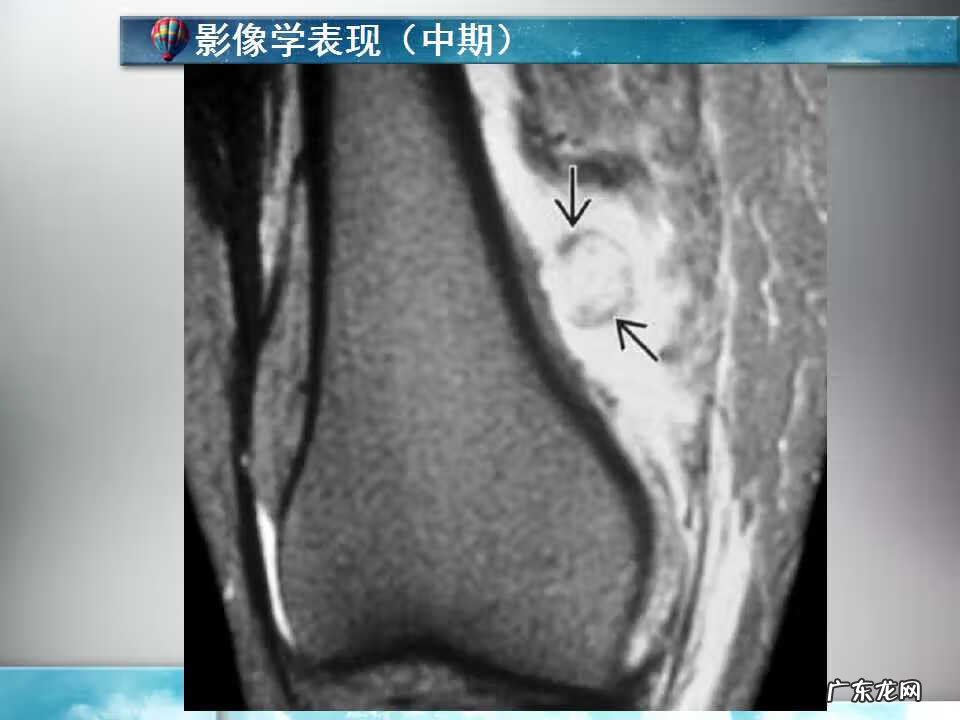

骨化性肌炎是由于关节内或关节附近发生骨折、脱位后 , 固定不良、反复粗暴的整复骨化性肌炎手法、被动活动 , 或在脱位后不久、骨膜重新与骨相连之前 , 过早地进行被动和强力活动 , 使纤维组织增生 , 骨或骨化生所致 。祖国医学认为:是因外伤瘀滞、气血失和 , 瘀血和筋膜交织 , 日久形成包块、硬结 , 引起血肿骨化 。多发于关节、股死头肌、内收肌、上臂肌、小、臀、膝、肩、肘等部位的肌肉处 。

病变组织多为肌肉 , 也可为筋膜、肌腱、骨膜 。肌肉受伤后成纤维细胞与间胚叶细胞增殖 , 酷丝纤维肉瘤或肌肉肉瘤 。细胞分区具有特征性 , 中心区为高度聚集的细胞 , 其外围是成纤维细胞组成的第二区带 , 再由成熟的能够定位的新骨组成第三区带 。当中心区有因出血形成的血池时组织像似巨细胞瘤 , 应注意鉴别 。发生于筋膜者表现大致同上 , 但不含有肌纤维 。而发生于肌腱止点者可形成一外生骨疣 。发生于骨膜者最终可致骨软骨瘤 。

(1)外伤性骨化性肌炎也称局限性骨化性肌炎 , 只显单一病灶 。多见于30岁以前 。常发生在外伤后 , 也有少数病例为并发与其他疾病者 , 例如发生在偏瘫、脊髓前角灰白质炎脊髓前角灰白质炎 , 烧伤或破伤风病人 。外伤后 , 软组织内出血可能是造成骨化的原因 。常于外伤2-3周后 , 在软组织出现钙化及骨化 。病变常出现在易接受外伤的部位 , 如肘、股、臀部 。在邻近长骨的骨干部分沿骨干的方向排列 , 呈层状骨化 , 而且于一处或数处可与邻近骨相联 。病变很少伸延到骨端及关节的部位 。骨化好发与肱前肌 , 表现为肘关节区肿胀与疼痛 , 肘关节被动与主动活动均受限 。疼痛与肿胀减退后在肘关节前方可以摸到一个界线清楚的硬的肿块 。因肌肉无弹性 , 故肘关节伸屈受限;由于肿块的阻挡 , 屈曲也明显受限 。x线特征:受伤后不久可出现局限性肿快 。伤后3-4周 , 在肿快内显示毛状致密象 , 其临近骨将显示骨膜反应 。伤后6-8周 , 病变边缘部清楚地被致密骨质所包绕 , 而具有新生骨的外貌 。软组织肿块的核心部有时显囊性变且逐渐扩大其内腔 , 到晚期而显出类似蛋壳状的囊肿 。伤后5-6个月肿块收缩 , 因而肿块与邻近的骨皮质和骨膜反应之间显出x线透亮带 。